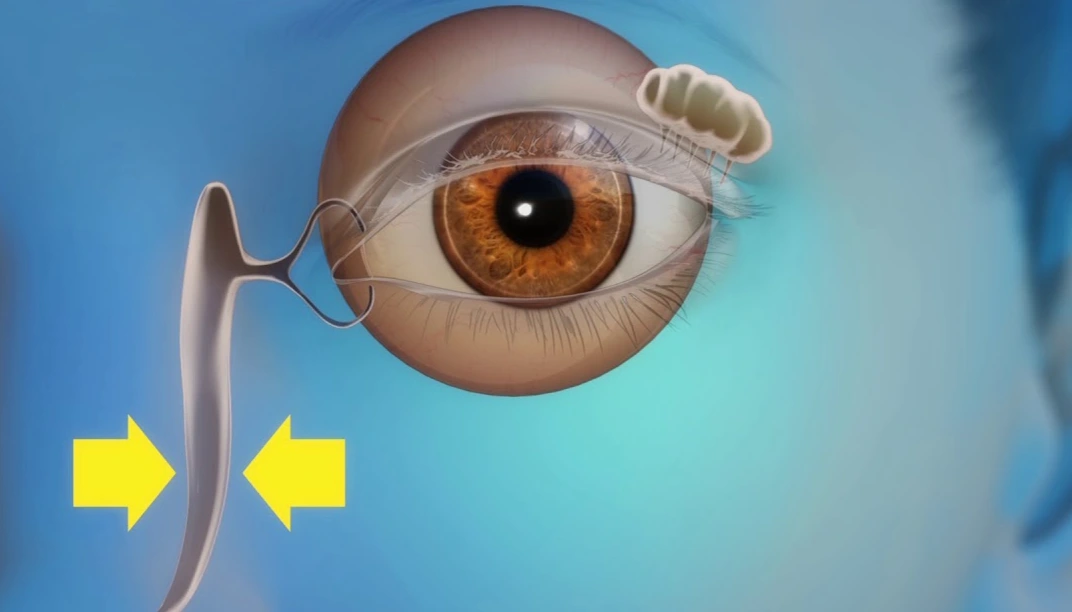

جراحة الأجفان ومجرى الدمع

انتفاخ العين أو التورم حول العين عادة ما يشير إلى تراكم مفرط للسوائل في أنسجة الجلد المحيطة. التهاب العين عند الأطفال قد يكون بسبب انسداد القناة الدمعية

استشاري جراحة تجميل العيون والجهاز الدمعي

الدكتور طارق النجار

استشاري جراحة تجميل العيون والجهاز الدمعي